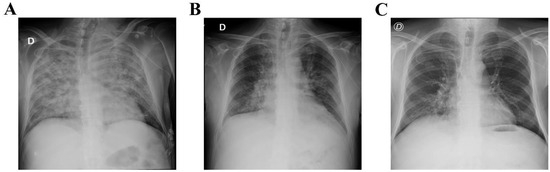

Successful Use of Ecmo in the Treatment of Acute Respiratory Distress Syndrome Associated with Sars-Cov-2 in Two Pediatric Cases

by Mariia Stasiv, Volodymyr Mishchuk, Natella Basa and Halyna Lytvyn

SARS-CoV-2 infection, in the vast majority, affects adult patients. The severity of COVID-19 and mortality are directly correlated with the increasing age of patients and the number of comorbidities. However, with the further development of the COVID-19 pandemic, severe cases of COVID-19 have been reported in children. About 0.8–1% of sick children require hospitalization in an intensive care unit. The main syndromes that cause disease severity and mortality in children are acute respiratory distress syndrome, multisystem inflammation syndrome and multiple organ failure. The rapid development of severe respiratory failure and hypoxemia in respiratory distress syndrome leads to the use of various methods of respiratory therapy, and in case of their ineffectiveness to extracorporeal membrane oxygenation (ECMO). In our report, we present two clinical cases of successful use of ECMO in children with COVID-19, who developed severe ARDS. Full article

Show Figures